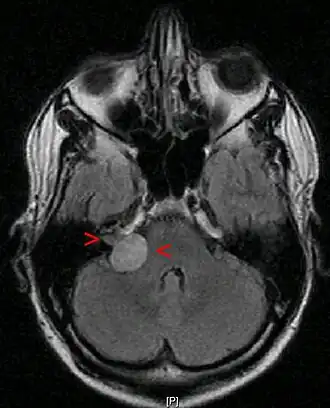

На МРТ выявляется ровный контур опухоли и по её периферии полоска сигнала так называемой «ликворной щели», деформация мозжечка и ствола головного мозга. При распространении невриномы во внутренний слуховой проход внекананальная её часть имеет вид «свисающей капли»[30].

Приблизительно 2/3 неврином выглядят гипоинтенсивными, а одна треть изоинтенсивными на Т1-взвешенных томограммах. На Т2-взвешенных томограммах невриномы характеризуются повышением сигнала, степень которого варьирует. Участки гетерогенно изменённого сигнала (вследствие образования кист) характерны для новообразований больших размеров (как правило, более 3 см). Все невриномы интенсивно накапливают контрастные вещества, более чем в 70 % случаев их накопление гетерогенно[30].